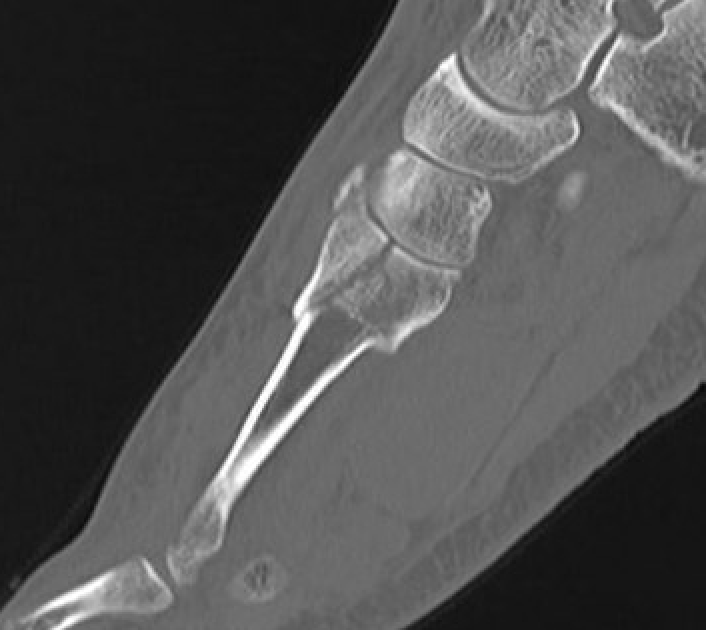

CT

Bone Scan / MRI

Show increased activity prior to xray changes